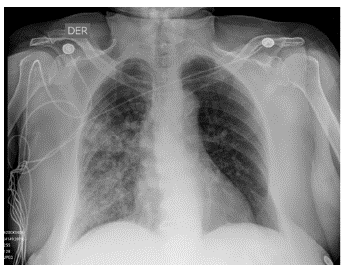

Al cuarto día de ingreso, tras ser trasladada de urgencias a sala de hospitalización, la paciente presentó hemoptisis espontánea durante la noche, con hipoxemia en reposo (SatO2 hasta 85 % con FiO2 0,21; al ingreso a urgencias, SatO2 94 % con FiO2 0,21) precisando suplementación de oxígeno a bajo flujo por cánula nasal, sin deterioro neurológico ni signos de dificultad respiratoria diferentes a ligera taquipnea (entre 30-35 respiraciones por minuto). Se documentó trombocitopenia grave (1000 plaq/ μL) y anemia moderada (hemoglobina 10,2 mg/dL). La gasometría arterial con una FiO2 del 32 % reportó: presión arterial de oxígeno (PaO2) de 61 mmHg, presión arterial de dióxido de carbono (PaCO2) de 28,6 mmHg y pH de 7,4. Paralelamente, se realizó una radiografía de tórax portátil con evidencia de opacidades heterogéneas bilaterales con aspecto de vidrio esmerilado predominantemente en el lóbulo medio e inferior derecho (Ver Figura 1). La paciente fue trasladada a unidad de cuidados especiales para vigilancia estrecha.

Figura 1 Radiografía de tórax (proyección AP) que muestra opacidades alveolares heterogéneas principalmente en el lóbulo medio e inferior del pulmón derecho. En general, la característica típica en la radiografía simple durante una hemorragia alveolar difusa aguda es un patrón de "opacidades alveolares bilaterales difusas". A veces puede haber una ligera predilección por las zonas medias, preservando lóbulos apicales.